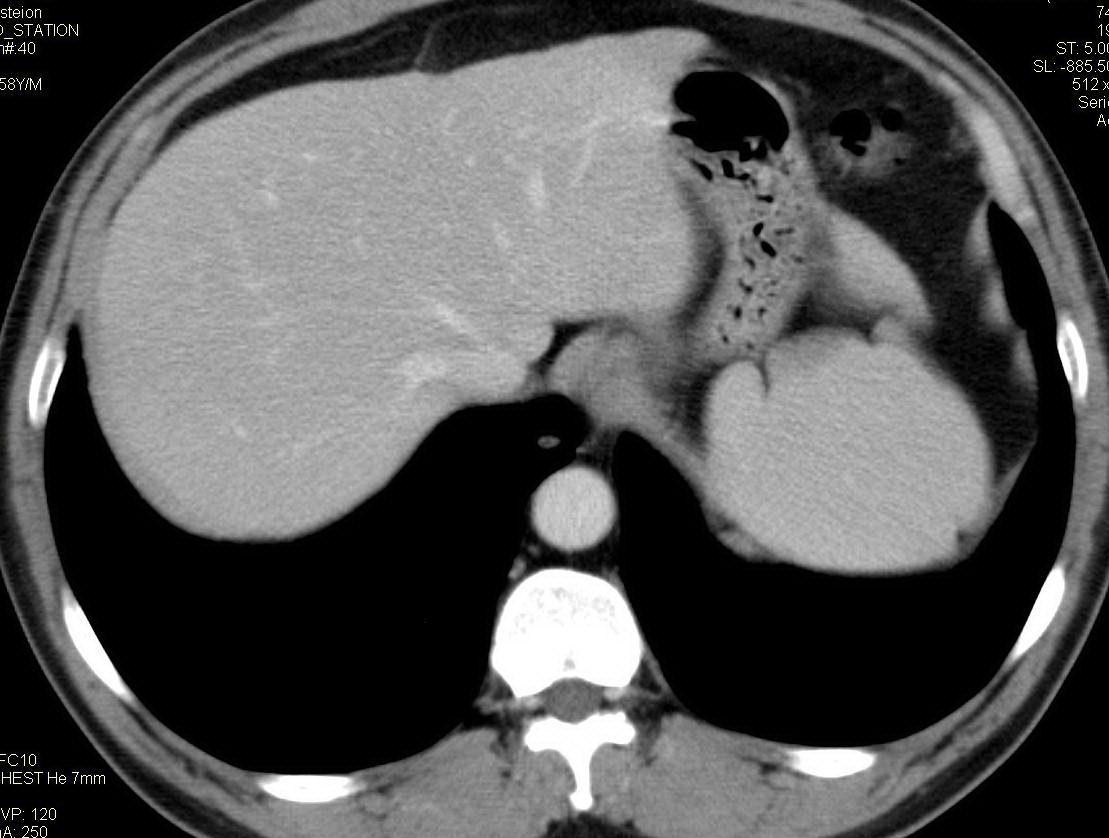

标题: CT15857:男性 58岁 咳痰带血 无发热 请各位大侠发表一下意见 [打印本页]

标题: CT15857:男性 58岁 咳痰带血 无发热 请各位大侠发表一下意见

两肺下叶肺纹理增多、增粗并呈“树芽状”改变。支气管扩张呈囊状,部分呈柱状改变。其周围可见散在的斑片样及条索样密度增高影,右肺下叶近叶间胸膜可见一形态不规则的高密度结节影,并与胸膜粘连。

双肺多发炎性病灶,结核可能性大,建议抗炎治疗复查.右肺下叶前基底段结节灶,高度警惕肺癌可能

双肺间质性改变(间质纤维化?)伴支扩。右肺下叶有毛刺的小结节,考虑周围型肺癌可能性。